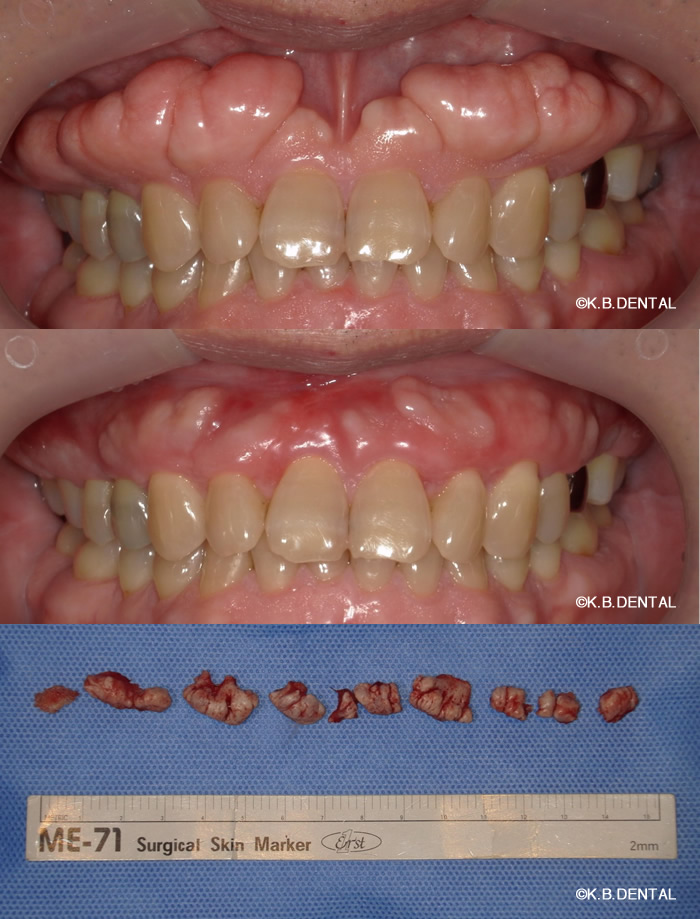

上顎外側骨隆起 症例2(上顎の頬側にできた骨隆起)

笑った時にゴボ口となりやすく、隆起した部分に食物残渣などが生じやすいケースです。静脈麻酔で約1時間半程度要します。

上顎外側骨隆起 症例3(上顎の頬側にできた骨隆起)